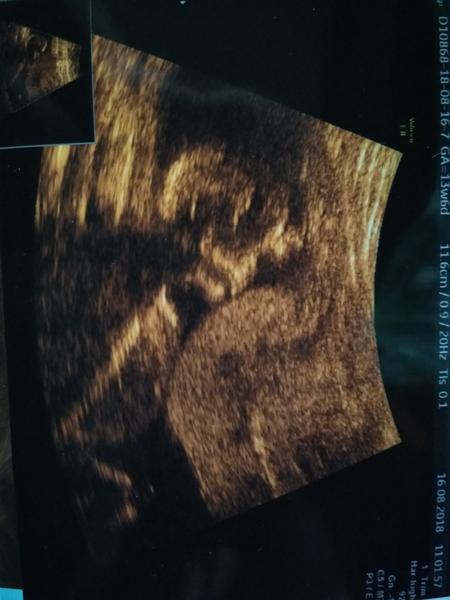

Ahojky holky 🙂 Tak jsem vás dočetla a konečně vám pisnu co screening 😍 Miminko podle ultrazvuku vypadá v pořádku, ještě uvidíme, jaké výsledky výjdou s krví 🙂 Ty budu mít v pondělí 🙂 Ale věřím, že budou negativní 🙏 Na ultrazvuku jsem byla zas 2x, mimčo nám ukazovalo pořád záda a prcku, tak jsem musela jít chodit, na druhý pokus se na chvilku prcek obrátil a hned šup zpátky opačně :D Ale to co se mělo vyšetřit se naštěstí stihlo 😂 Jinak pohlaví jsem si nechala říct jen já, zatím to je jasná holčička, tak uvidíme, jestli ji nenaroste pindík 😂 Manžel pořád sondoval 😂 Tak asi za hodinu jsem koupila 2 věci v barvě a potom mu to dala :D No a to jste měli vidět to nadšení 😂 Chvilku byl zklamanej, ale u jídla to rozdýchal, začal se těšit a šel si koupit na oslavu drahej doutník (nekouří, doutník si vždycky dá na vyjimečnou situaci, třeba když zapíjel první dvě) 😂 Tady je fotka, zrovna se zas natáčela zpátky, zádama k nám, takže fotka nic moc :D Foto oblečků pošlu, až mi usne mladší 🙂

Ještě jsem nenapsala, že mimčo odpovídá týdnu, je dnes 13+6, termín 15.2., takže nic se nemění :D Měří pomale 79 mm 🙂 Nosní kůstka je, projasnění v normě, srdíčko, mozek, pupečník, žaludek vše ok, tam kde má být 🙂